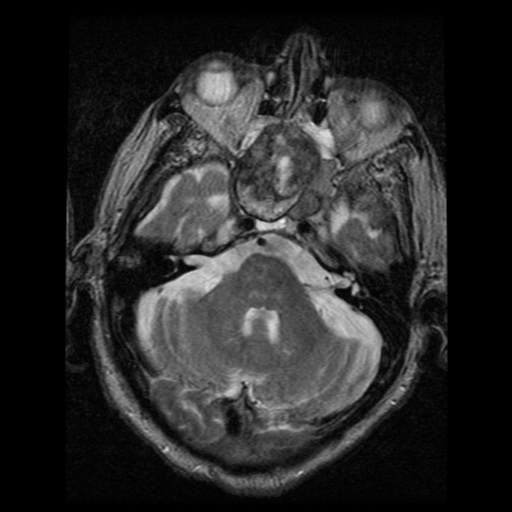

Ecchordosis Physaliphora

Cystic lesion in the prepontine cistern without enhancement or restricted diffusion extending into bone.

Absence of enhancement or restricted diffusion together with non-aggressive bony margins in this location is typical of a retroclival ecchordosis physaliphora, a notochord remnant.

Ecchordosis physaliphora is a congenital benign hamartomatous lesion derived from notochord remnants, usually located in the retroclival prepontine region, but can be found anywhere from the skull base to the sacrum.

Unlike chordomas which are often symptomatic due to brainstem or cranial nerve compression, patients with ecchordosis physaliphora are usually asymptomatic. They are found in ~2% of autopsies 1.

Ecchordosis physaliphora arise from remaining notochord cells along the axis of the spine after embryogenesis. Unfortunately, ecchordosis physaliphora and chordoma are histologically indistinguishable, other than by examining the margins, the latter demonstrating infiltrative growth.